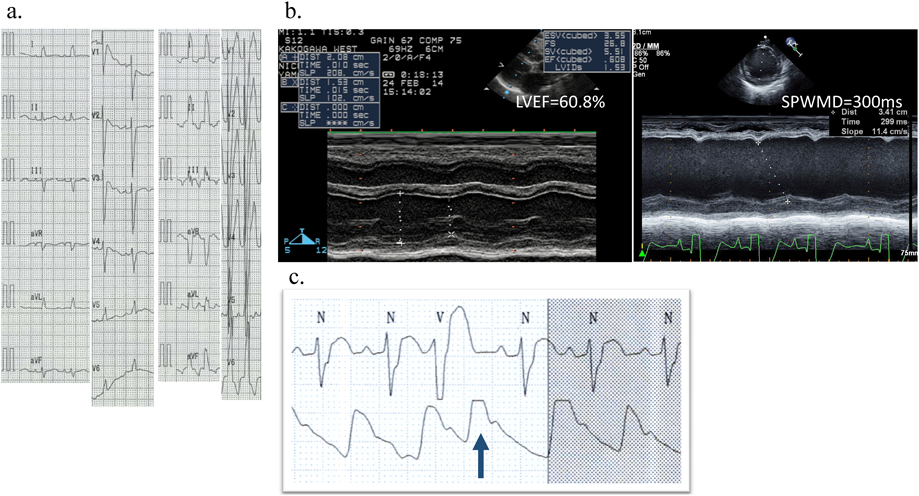

Fig. 3 Several laboratory findings that indicating the CRT adaptation in infants

a. 12 leads ECG at 10 days of life (left) and 4months (right) just before CRT-P implantation in Case 3. b. M-mode echocardiography at 10 days of life (left) and 4months (right) just before CRT-P implantation in Case 3. c. Interestingly, arterial pressure monitoring shows the significant elevation of pressure at a single ventricular premature contraction arose from LV.

成人の症例では左室リードは多極リードが使用できるようになり,植え込み後に任意のペーシング部位を選択できるようになった.一方,小児の場合は開胸でのリード植え込みとなるため,任意の場所に留置することができる反面,至適ペーシング部位の決定はCRTのoutcomeを左右する重要な問題である.左室の心室内非同期を改善させることが目的であることから,右室は流出路から心室中隔へ伝導させるか,心尖部から心室中隔へ伝導させるかどちらかということになる.現時点ではspeckle trackingでmechanicalなdelayを評価して再遅延部位を指標に左室リードを逢着するのがいいと考える.Fig. 3bに示す例ではseptal to posterior wall motion delay(SPWMD)で見ると,中隔と左室後壁にmechanicalな収縮時相のズレが認められる.このmechanicalな収縮時相のズレを局所の非同期性だけでなく,心室全体の動きについて収縮期の時相のずれを見ることができるのがspeckle tracking法(Movie 1)である.Fig. 1a, bにCRT-Pシステムの植え込み前後のレントゲンを示す.右房,右室,左室の3カ所にリードを逢着するため,BipolarリードよりUnipolarリードを選択することも心臓の絞扼性障害を避けるためには有効な手段である.

術前は非常に強い肺うっ血が特徴である.強心薬の使用は時に心室内非同期や心室間非同期を強くして状態を悪化させることもあるので注意が必要である.すなわち,改善でき得る心室内(間)非同期が存在する場合は,非同期を改善させた後に慢性心不全治療へ移行することが望ましいと考えられる.すなわち,CRTは急性期治療の一つとして位置付けられるものである.よって可及的速やかにdyssynchronyの評価を行い,CRT治療を行った上で慢性心不全治療の導入を行う必要がある.時に,術前の管理のなかで期外収縮がストレッチした左室より起こることがある.その場合は左室起源の期外収縮により観血的動脈圧モニターで血圧上昇が観察されることがある.これはすなわち左室ペーシングで血圧が上がる可能性を示唆し,CRTによる急性効果を予測させる所見となり得る(Fig. 3c).